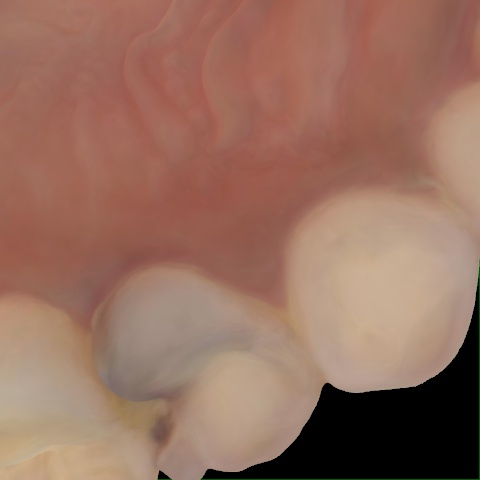

Incorrect Quality Level

The reference annotation for this image is

None

.

Please select the correct quality level.

Image 142 / 1103

Annotated as "Good"